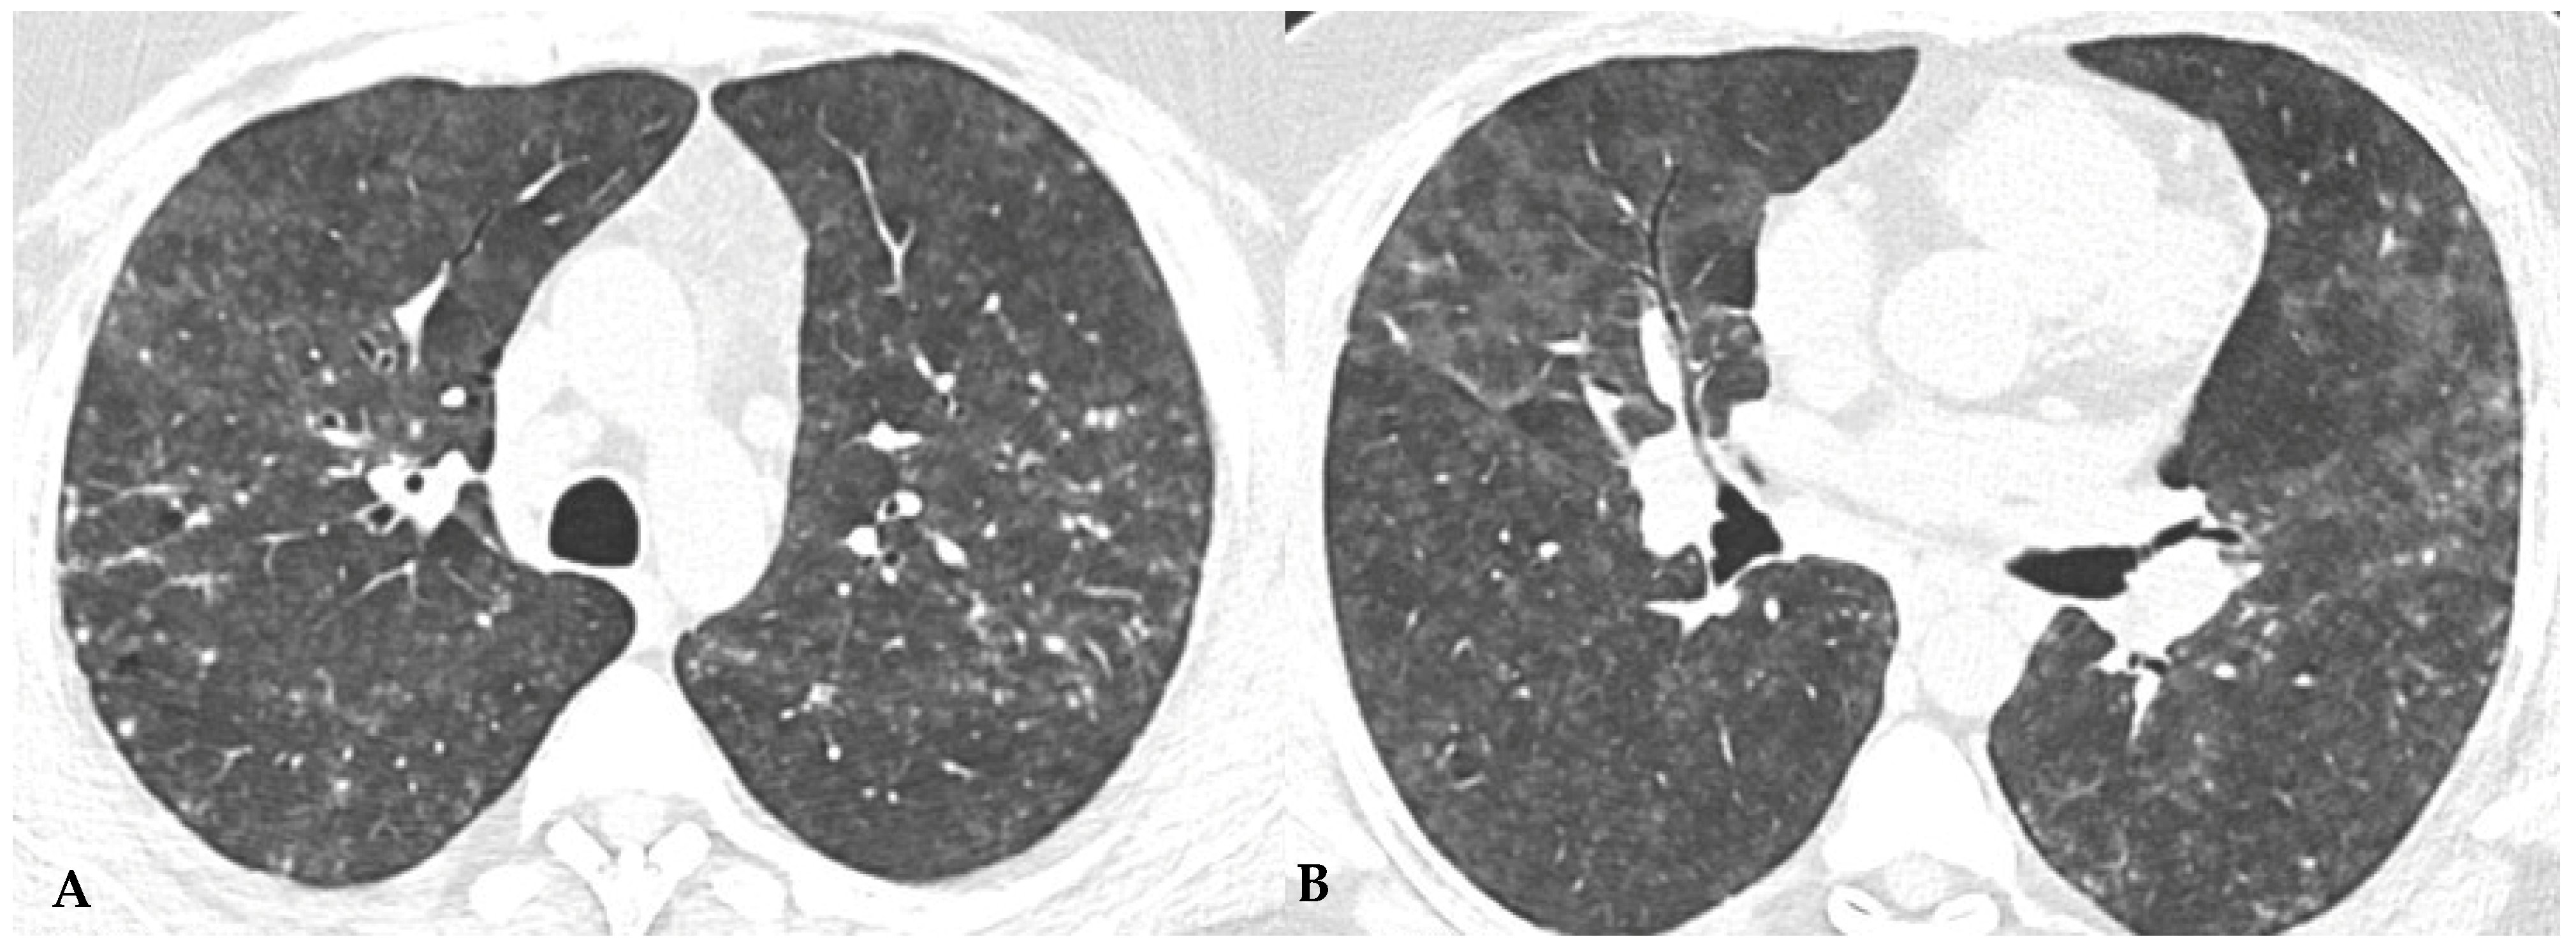

Figure 9.

Truly indeterminate HP pattern. Chest HRCT, axial scan HRCT pattern characterized by mild fibrotic changes of a limited extent with patchy GGO in the upper lobes (A); the lower lobes show GGO, fine reticulations with modest mosaic attenuation and rare traction bronchiectasis/bronchiolectasis (B) with a “truly indeterminate” pattern according to new HP guidelines (2020) [4].

Figure 10.

f-NSIP pattern: chest HRCT, axial scan. Mild fibrotic changes of limited extent with a greater distribution in the upper lobes with superimposed GGO (A); the lower lobes show marked extension of GGO, fine reticulations with traction bronchiectasis/bronchiolectasis (B); “fibrotic NSIP pattern” according to new HP guidelines (2020) [4].